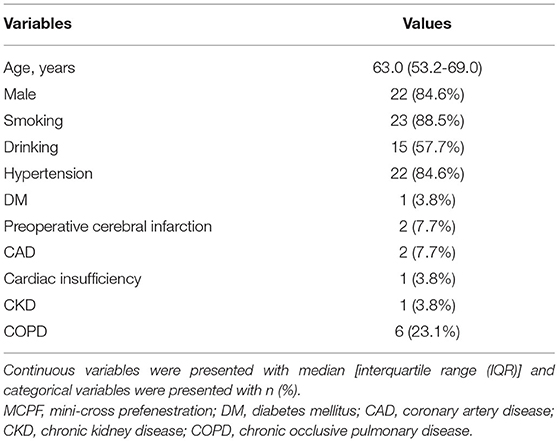

The main stent grafts were 34 mm Valiant Thoracic Stent Grafts, which were generously donated by Medtronic Vascular, Santa Rosa, California, USA. All the 12 main stent grafts were released, prefenestrated with a 5 × 5 mm cross (Figure 1A), and then delivered into the silicone aortic models. There were 12 Fluency Plus Stents (Bard Peripheral Vascular, Tempe, Arizona, USA), in which the sizes were 7 × 60 mm (3 stent grafts), 8 × 40 mm (3 stent grafts), 12 × 80 mm (3 stent grafts), and 13.5 × 40 mm (3 stent grafts). The delivery system came through the fenestration (Figure 1B) and slowly released the stent grafts when tips passed 2–3 cm (Figure 1C). When the branch stents were completely released from the delivery system (Figure 1D), a 10 × 40 mm balloon (Mustang, Boston Scientific, Natick, Massachusetts, USA) was delivered to furtherly enlarge the orifice of the branch stents (Figures 1E,F).

Figure 1. In-vitro experiment on the MCPF stent grafts in silicone models. (A) Release of the Valiant Stent Graft (diameter 34 mm and length 150 mm) with a 5 × 5 mm cross prefenestration (black square). (B) The hole of the fenestration is suitable to come through for an 8 Fr catheter delivery system (Fluency Plus Stent, diameter 80 mm and length 80 mm). (C) Release of the branch stent. (D) Top view of the branch stent after release. The hole was slightly expanded by the self-expanding force (white arrow). (E) The stent graft was flared with a peripheral angioplasty balloon at 4 atmospheres (Bard Mustang, diameter 10 mm and length 40 mm) (black arrows). (F) The stent graft was completely flared at 6 atmospheres (blue arrows). MCPF, mini-cross prefenestration.